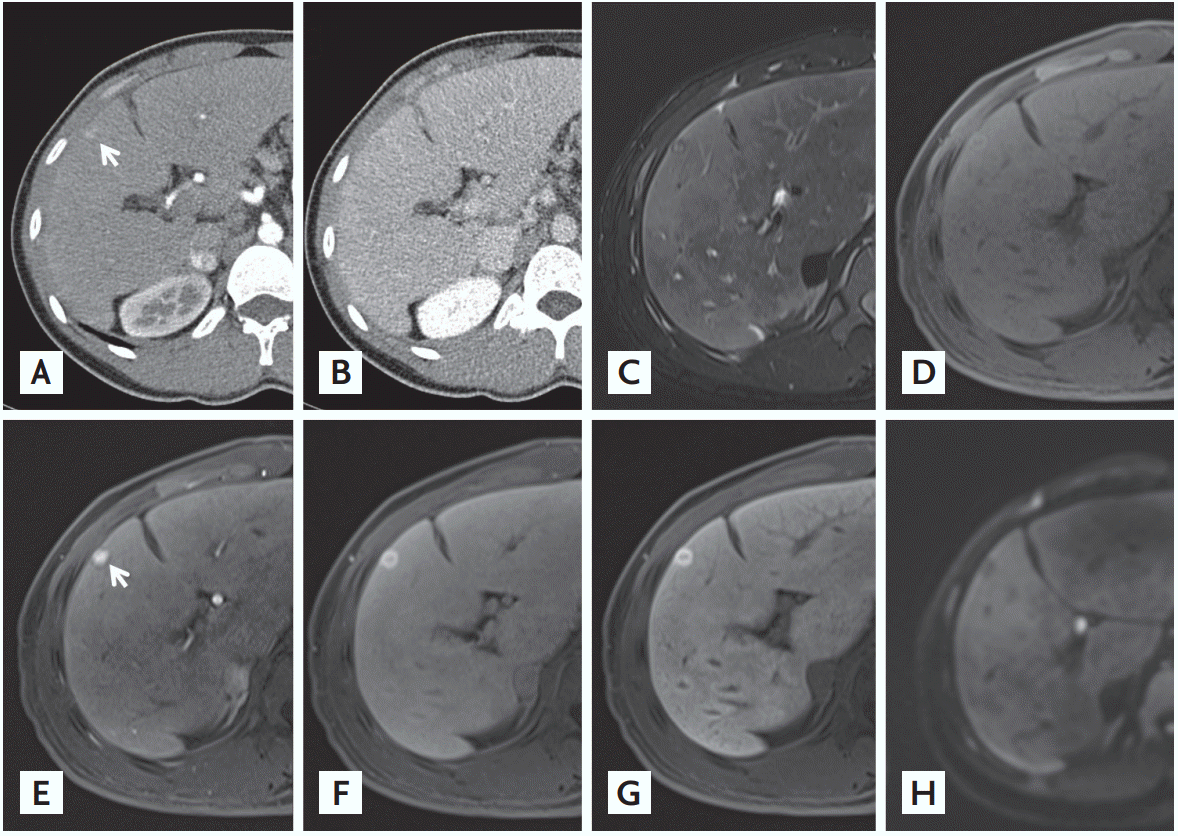

A 23-year-old male patient who had been diagnosed with cryptogenic cirrhosis 30 months earlier presented with a tumorous lesion in the liver that increased in size from 4 to 11 mm in the past 15 months. Contrast-enhanced computed tomography (CT) demonstrated a 1.1 cm-sized nodule in segment 4 of the liver with arterial hyperenhancement (Fig. 1A) and delayed phase washout (Fig. 1B), compatible with typical features of hepatocellular carcinoma (HCC). The nodule showed hypointensity with hyperintense central foci on a T2-weighted image (Fig. 1C) and subtle hyperintensity on T1-weighted magnetic resonance imaging (MRI) (Fig. 1D). After the injection of gadoxetic acid, strong homogeneous arterial enhancement without washout appearance (Fig. 1E) and hyperintensity on the transitional phase image were present (Fig. 1F). On the 20-minute hepatobiliary phase (HBP) image, the nodule showed hyperintensity with central hypointensity (Fig. 1G). There were no areas of diffusion restriction on a diffusion-weighted image (b = 800 s/mm2) (Fig. 1H). The lesion was pathologically diagnosed as a focal nodular hyperplasia (FNH)-like nodule arising from cryptogenic cirrhosis (Fig. 2).

Figure 1.

Contrast-enhanced computed tomography (CT) shows a 1.1 cm-sized nodule in segment 4 of the liver (arrow) with (A) arterial phase and (B) delayed phase washout. (C) The nodule shows hypointensity with hyperintense central area on a T2-weighted fat suppressed image, and (D) slight hyperintensity on a T1-weighted fat suppressed image. (E) After the injection of gadoxetic acid, the nodule is homogeneously hyperenhanced on the arterial phase (arrow) with (F) hyperintensity on the transitional phase image. (G) On the 20-minute hepatobiliary phase image, the nodule is hyperintense with central area showing hypointensity (“ethoxybenzyl [EOB] scar”). (H) There are no areas of diffusion restriction on diffusion-weighted image.